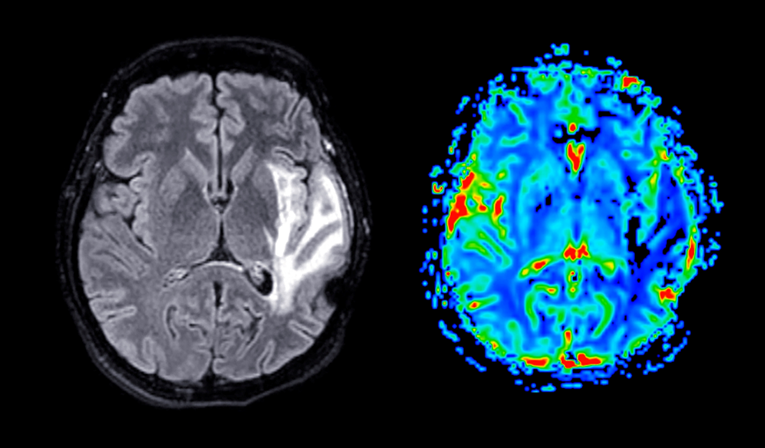

Kako je navedeno u novoj studiji međunarodnog tima istraživača objavljenoj u časopisu PNAS, mozak se "pomakne prema gore i unatrag unutar lubanje nakon svemirskog leta, pri čemu senzorna i motorička područja pokazuju najveće pomake". Istraživači su također otkrili da se oblik mozga deformira na mjerljive načine, a te se promjene samo ponekad vrate u normalu unutar šest mjeseci nakon povratka na Zemlju.

Tim je analizirao podatke magnetske rezonancije (MRI) 26 astronauta i usporedio ih s kontrolnom skupinom. Usporedni podaci prikupljeni su tijekom "dugotrajne studije mirovanja u krevetu s nagibom glave prema dolje", koja je uključivala 24 sudionika koji nisu astronauti. Njima je naloženo da leže pod nagibom od šest stupnjeva s glavom ispod razine stopala do 60 dana.

Rezultati su pokazali da je svemirski let uzrokovao pomicanje mozga astronauta prema gore i natrag, a stupanj pomaka bio je povezan s trajanjem izloženosti svemiru. Mozgovi sudionika u studiji mirovanja također su se pomaknuli unatrag, ali ne i prema gore u istoj mjeri kao kod astronauta, što sugerira da svemirski let ima izraženiji učinak.